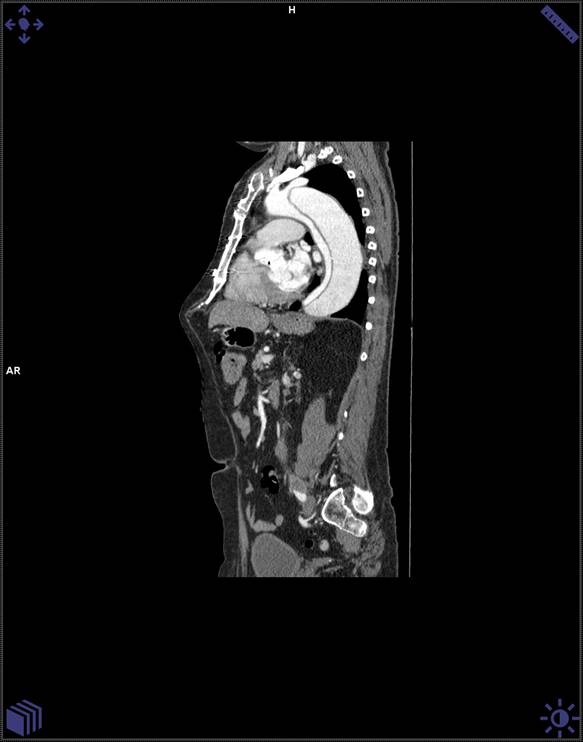

Caso 62

La TC es la técnica de imagen diagnóstica más frecuentemente empleada en los pacientes en los que se sospecha disección aórtica. Sus valores de sensibilidad y especificidad superan el 90 y el 85%, respectivamente. Entre sus principales virtudes están el poder detectar fácilmente la localización de la disección aórtica, si están o no implicadas las ramas arteriales y la existencia de los denominados «signos de emergencia», como puede ser la existencia de sangre en el mediastino, que implican una necesidad urgente de tratamiento quirúrgico para el paciente.